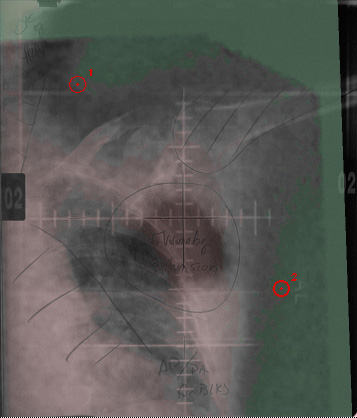

In this tutorial we will fuse the sample chest x-ray and gallium scan that come with the Madena download. The same principles would apply to any other fusion, such as a CT and an MR image.

The chest and gallium .jpg files were obtained using a hand-held megapixel digital camera and simply taking a "snapshot" of the films as they hung on the backlit film viewer. The chest x-ray was 14"x17", the gallium scan about 3"x2". The .jpg files were transferred to a PowerMac running OS-X via USB and cropped in Photoshop 7.

1. Set the "Image AB" button to A and open the chest.jpg file as image #0. Use the bias and gain controls to visualize the tangential skin surface as much as possible. A physician had outlined the approximate location of the tumor on this film before it was digitized. Lets see how well he did.

2. Enable Point-of-Interest (POI) drawing by clicking the "POI" button and place at least two (or more) points on image A at locations that you can identify in both images. POIs are placed by simply clicking on the image. When you have placed your points, click the POI button again to disable POI drawing. You can drag the POIs on the image by simply clicking on them. You can delete POIs by shift-clicking on them. The currently selected POI (#2 in the example below) is marked by a thicker circle. The "Points" menu provides additional options for the currently selected POI.

4. Set the "Image AB" button to B and open the gallium.jpg file as image #1.

5. On image B, mark the same number of points, and in the same order as you did on image A. In the gallium example below I have applied a green tint across the gray range 0..120 to help define the tangential skin surface. The large black spot is the tumor. Our objective is to find the equivalent location of the tumor on the chest x-ray.

7. Switch back to image A (the chest image) by clicking the "Image AB" button.

8. In this example I applied a pink tint to the chest image across the range 122..255. It can help with visualization if you apply contrasting tints to the images being fused.

9. Click the "Fuse" button to enable image fusion. The images will fuse but the secondary image (ie image B in this case) is much smaller than the primary. Next, click the "Fit" button. The secondary image will be rotated and scaled to match its POIs to the equivalent POIs on the primary image. If you click the "Image B" button and then click the "Fit" button the fusion will work the opposite way, ie image A will be scaled and rotated to fit image B. (Shortcut: simply clicking the Fit button will automatically enable fusion for you.)

11. slider The fusion slider controls the balance between the two source images. The "Tiles" slider divides the image into alternating tiles from the primary and secondary images. The "Diff" button provides some alternate fusion methods such as addition, subraction, multiplication and division of one image by the other. Control-click on the "Diff" button for a contextual menu.